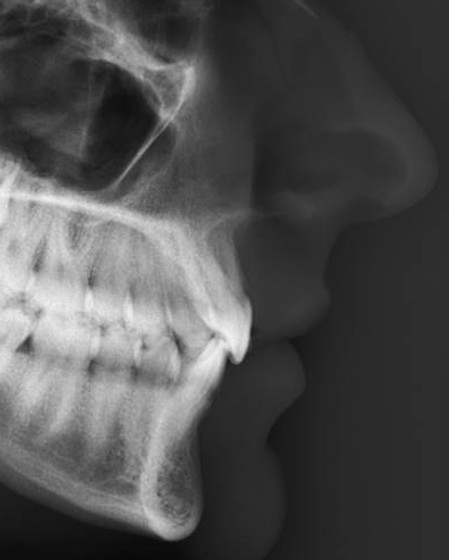

Ponto Subespinhal (A)

Ponto médio mais profundo da pré-maxila, entre a espinha nasal anterior e o próstio (William B. Downs 1948).

A